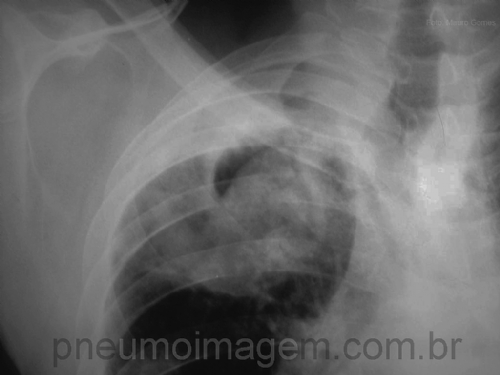

CASO CLÍNICO #13

Paciente com histórico de tuberculose apresenta-se com hemoptise e a seguinte imagem radiológica. Qual o diagnóstico mais provável? Deixe os seus comentários abaixo.

Patient with previous tuberculosis presents with hemoptysis and the following radiological image. What is the most probable diagnosis? Comment about the case below.